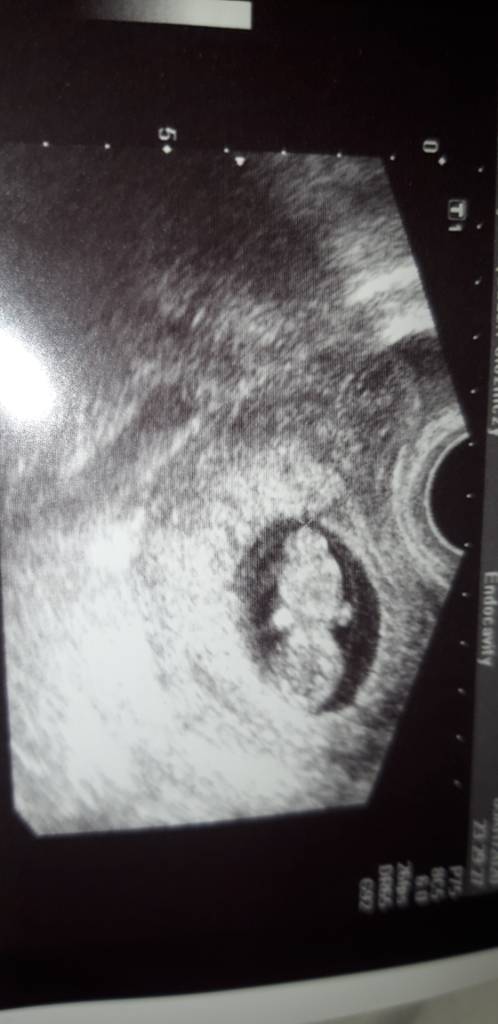

Hej ja jestem w 10tc skorzystałam z kd i jestem najszczęśliwsza ciężarna na świeciePowodzenia i dawaj znać jak efekty.

O rany..to swietnieHej ja jestem w 10tc skorzystałam z kd i jestem najszczęśliwsza ciężarna na świecie

Jeszcze raz gratuluje i zycze spokojnej ciazy![]()

Czekaliśmy ogólnie 1.5 miesiąca az zadzwonili że udało się pobrać 6 dojrzałych komórek i ze od jutra mam sie kontaktować z laboratorium w sprawie zarodków

Ale udało się i mamy 4blastki zamrozone

Prawie po tej informacji miałam wizytę u lekarza zaczęłam brać estrofem i 18dniu cyklu był transfer z mrozaczkiem

Zobacz załącznik 1064744